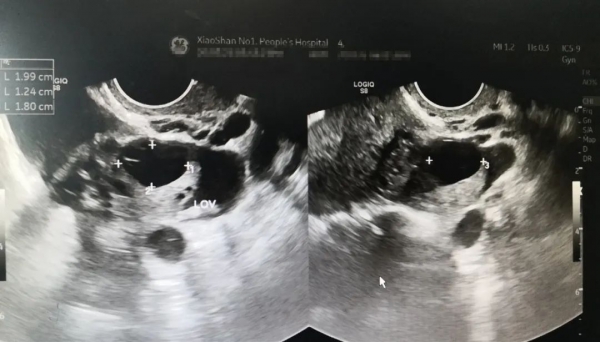

医生为小甜做了B超检查后发现,小甜的黄体破裂,肚子里出了不少血,需要马上手术治疗。在进一步询问下,小来才支支吾吾地说,今天晚上两个人在床上有点激烈,完事后小甜就说自己腹痛。

黄体是女性正常周期中的生理变化过程,女性排卵后残留的卵泡壁塌陷,卵泡膜的结缔组织、毛细血管等伸入到颗粒层,在黄体生成素的作用下演变成体积较大、富含毛细血管并具有内分泌功能的细胞团,新鲜时显黄色,一般会长到1-3cm,像个蛋黄一样。所以叫做黄体。

一般月经周期的第15到第28天内,被称为黄体期,而黄体最容易破裂的是黄体后期,一般是在月经来前一周左右。这个时候,如果遇到外力的冲击,比如下腹受到撞击、剧烈跳跃、奔跑、用力咳嗽或解大便时,腹腔内压力突然升高,会促使成熟的黄体发生破裂。